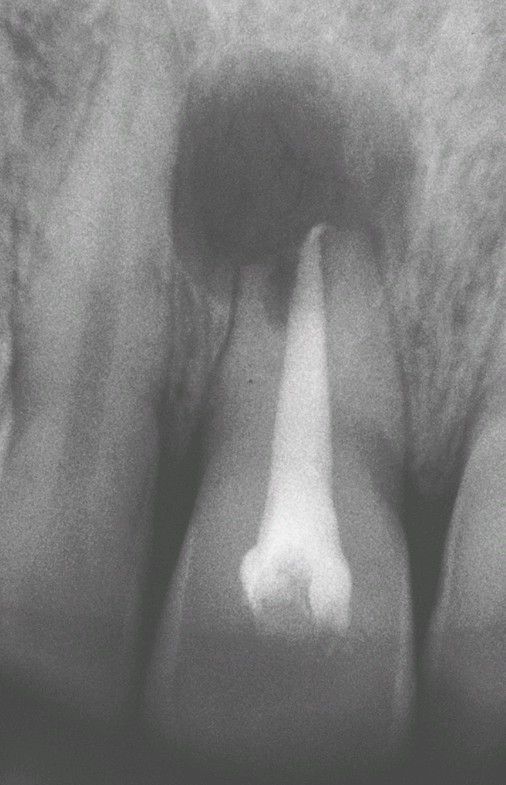

Periapical Cyst

. Radiolucency associated with the maxillary central incisor, which exhibits significant root resorption.